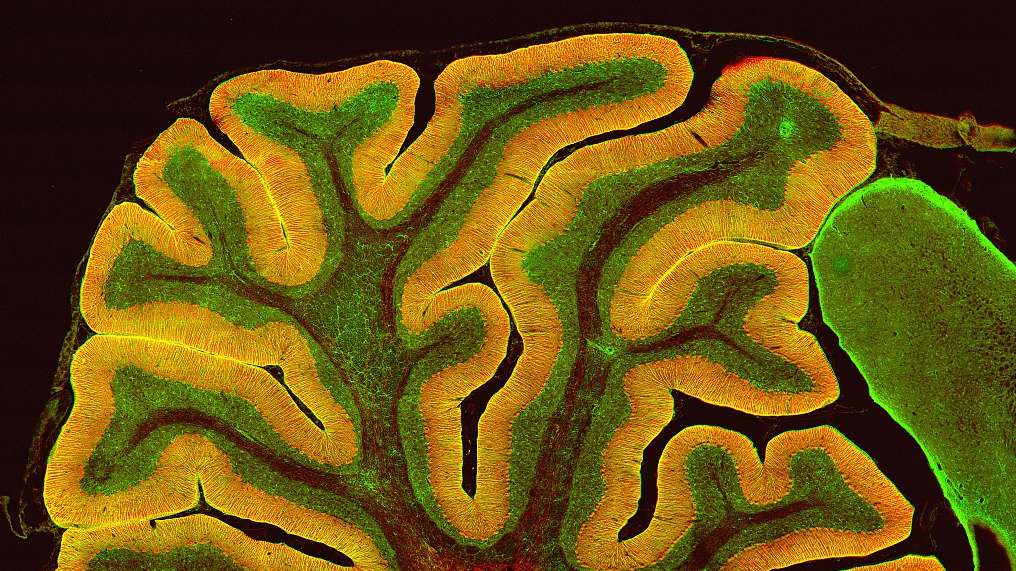

Researchers at the University of Illinois (UI) have identified a key protein involved in the irregular brain cell activity seen in autism spectrum disorders and epilepsy.

Using a mouse model of Fragile X syndrome, the most common inherited autism disorder, the researchers discovered a molecular mechanism involved in the inability to regulate excitability. The protein p53, well-known in cancer biology as a tumor suppressor, is present in higher-than-normal levels in irregularly excitable neurons.